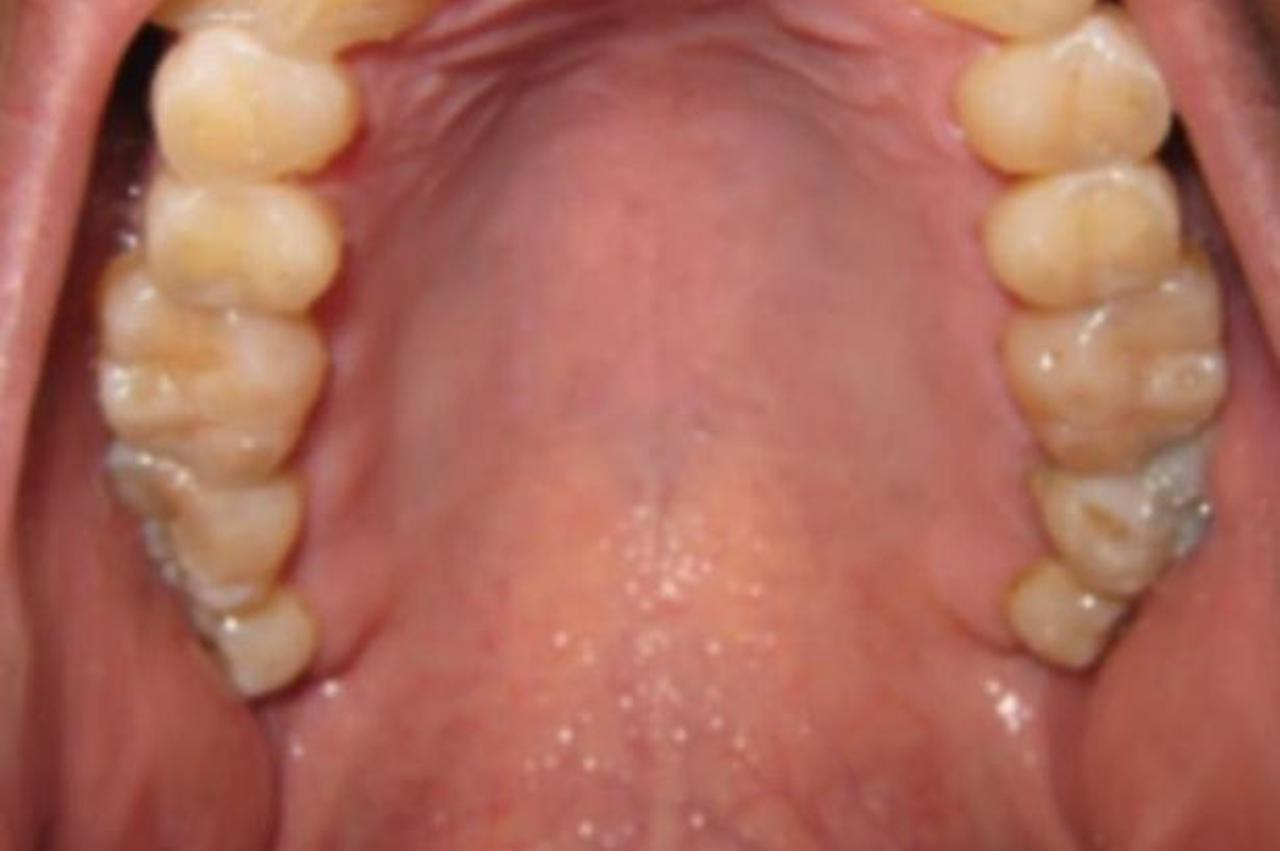

Došao na redovni pregled kod zubara pa mu on otkrio nešto neobično u ustima

Oni su u njegovoj usnoj šupljini, odnosno na nepcu, uočili crvene lezije koje su nastale zbog prakticiranja oralnog seksa